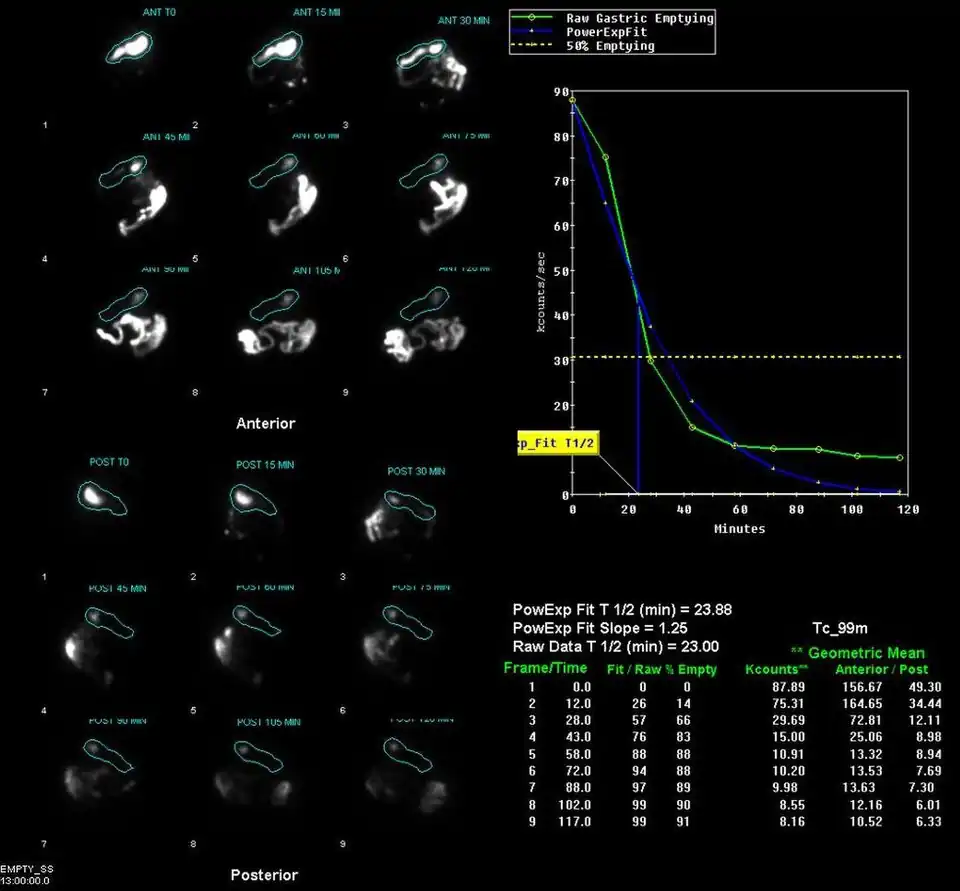

Example gastric emptying images | |

A gastric emptying study is a nuclear medicine study which provides an assessment of the stomach's ability to empty. It may be used if there are complications after gastric surgery, for gastric reflux, or suspected gastroparesis amongst other indications.[1] Scintigraphy that uses gamma cameras to create two-dimensional images is generally regarded as the gold standard for gastric emptying.[2][3]

Having fasted for around four hours before the study, the patient is given a solid or semi-solid meal, such as scrambled eggs on toast or porridge, which has been prepared with a radiopharmaceutical component. Typically technetium-99m sulphur colloid or DTPA is used.[4][1][5] Some studies may also involve a liquid component, which is labelled with indium-111 DTPA.[5] Images are acquired with a gamma camera, initially dynamically and then at intervals for up to 2-3 hours.[1][5][6]

The stomach time-activity curve is produced from geometric mean of anterior and posterior imaging. Half-emptying time, the lag-phase duration for solid studies, and percentage of food left at various time points are calculated.[7]